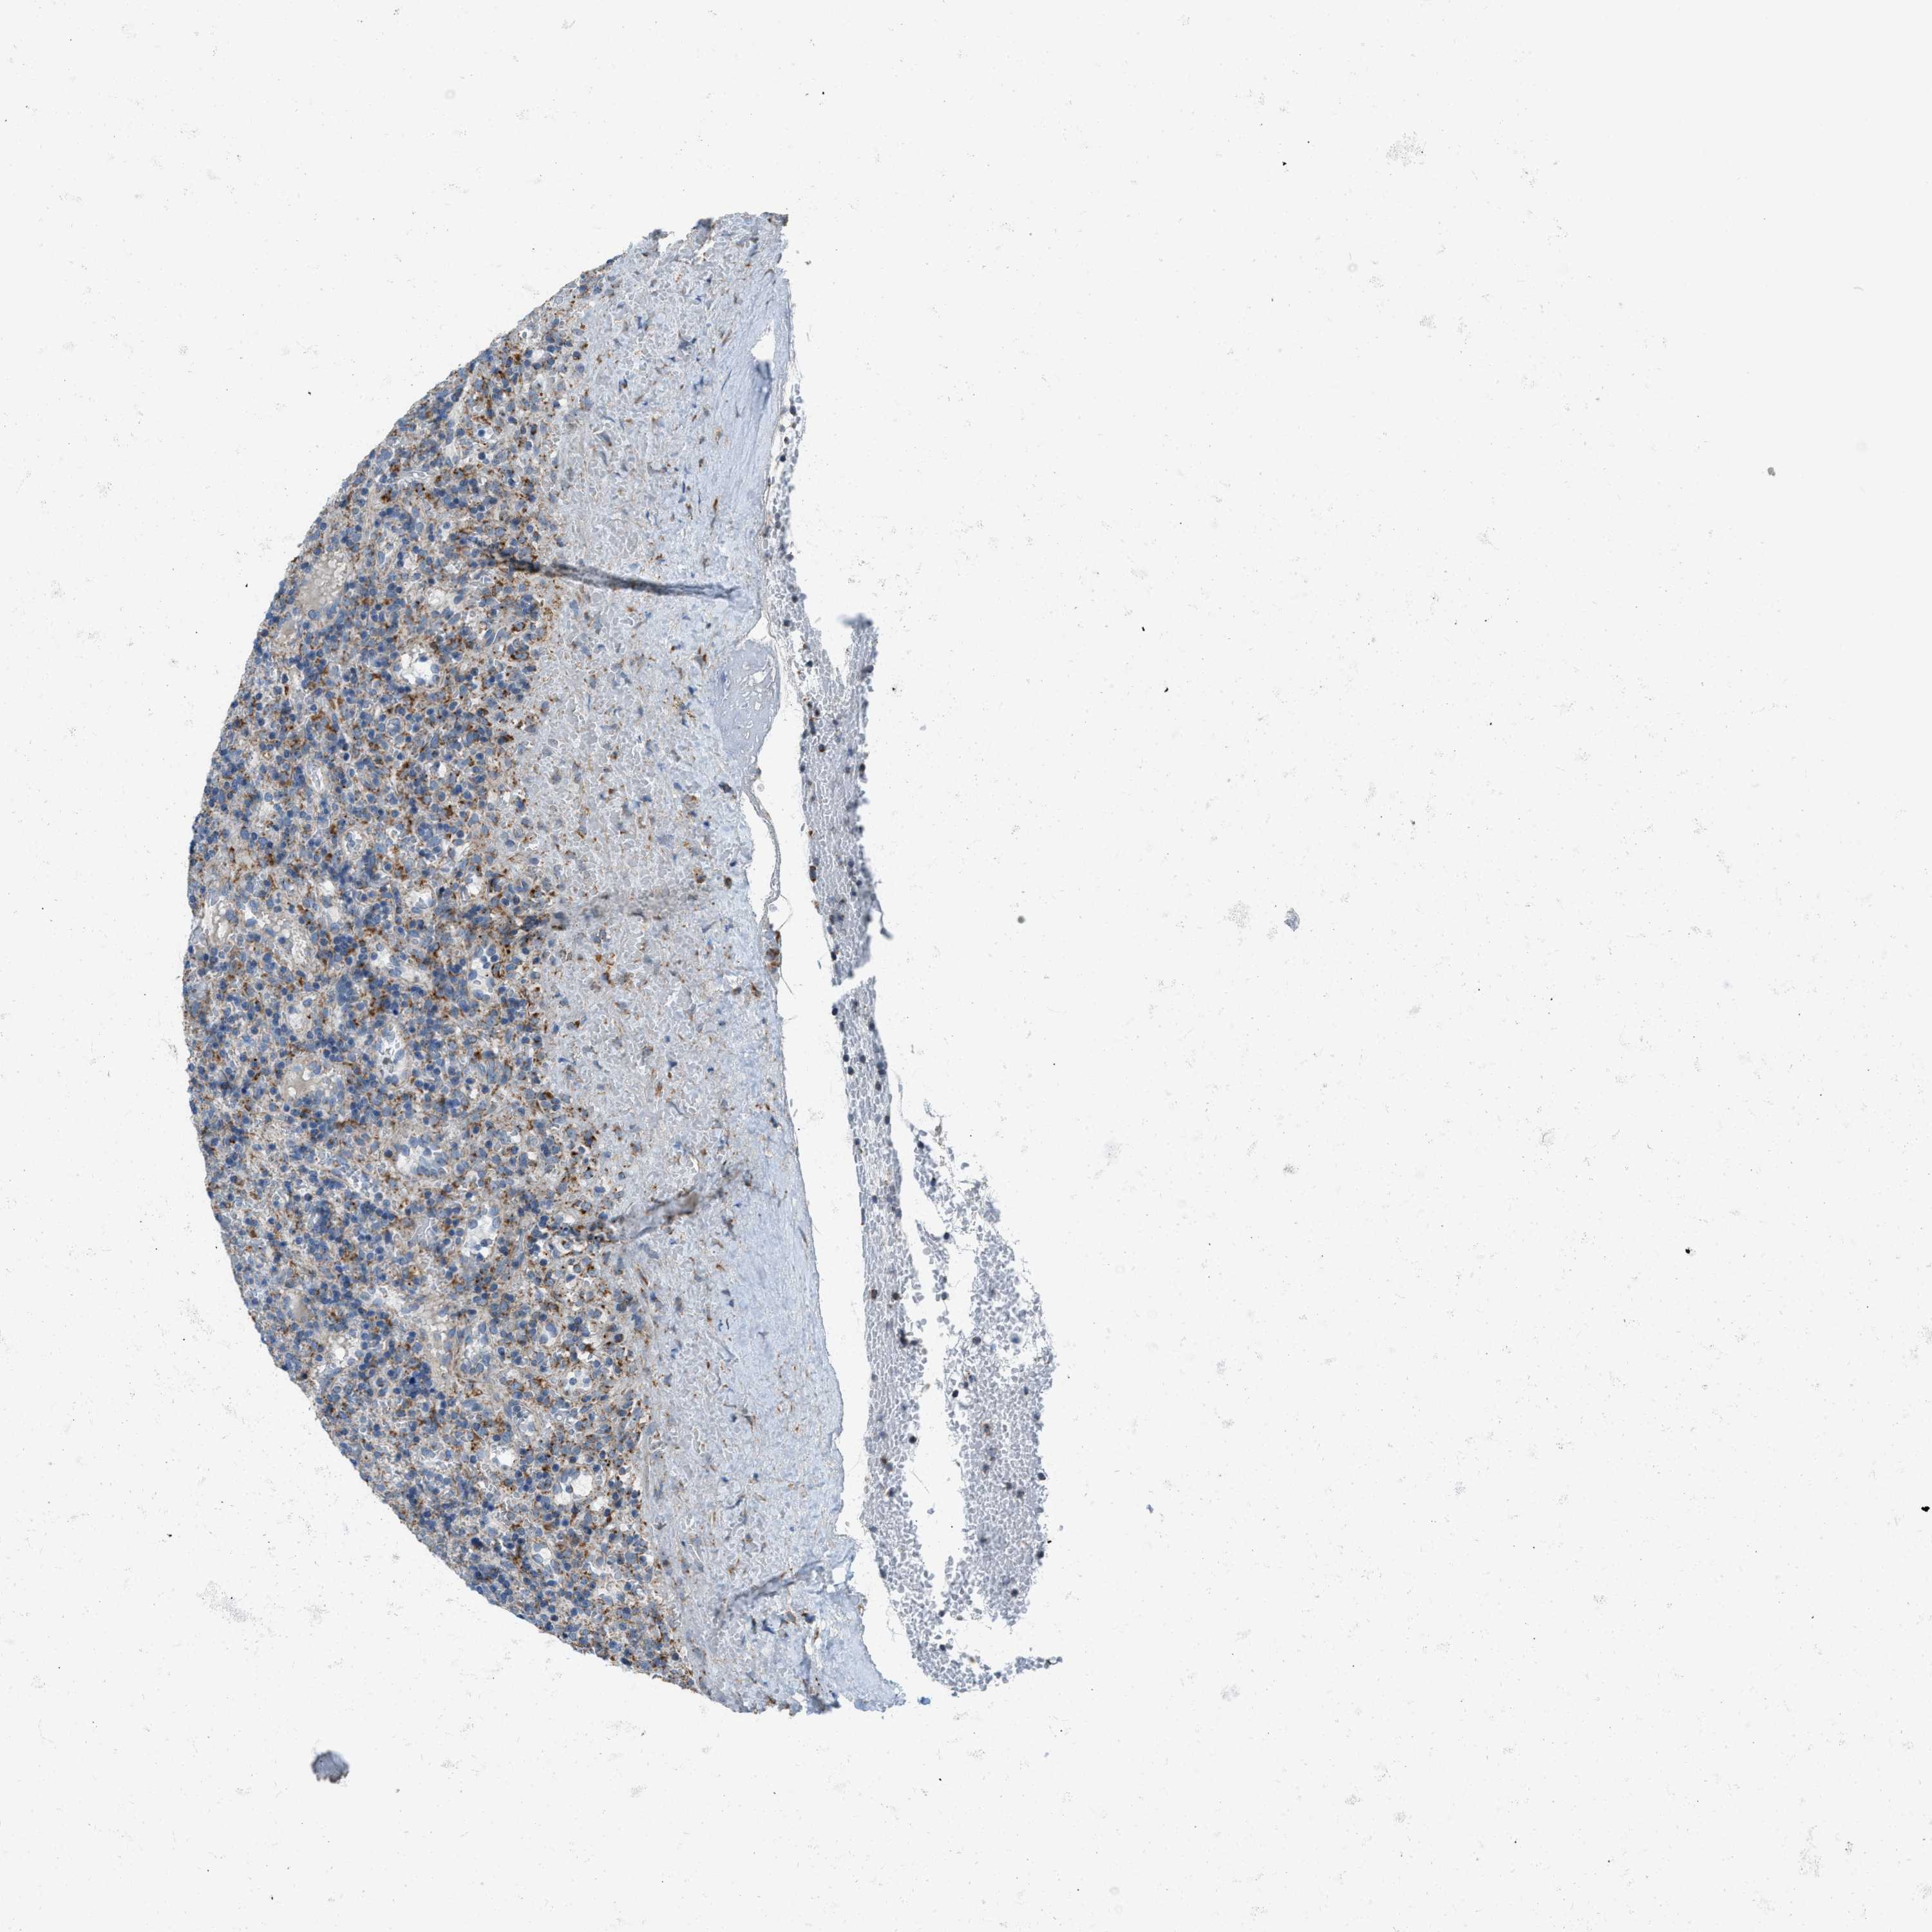

LYMPHOMA - Protein expressioni

A mouse-over function shows sample information and annotation data. Click on an image to view it in a full screen mode. Samples can be filtered based on level of antibody staining by selecting one or several of the following categories: high, medium, low and not detected. The assay and annotation is described here.

Antibody stainingi

Antibody staining in the annotated cell types in the current human tissue is reported as not detected, low, medium, or high, based on conventional immunohistochemistry profiling in selected tissues. This score is based on the combination of the staining intensity and fraction of stained cells.

Each image is clickable and will lead to virtual microscopy that enables deeper exploration of all samples and also displays staining intensity scores, fraction scores and subcellular localization as well as patient and tissue information for each sample.

Antibody HPA016552

Staining

High

Medium

Low

Not detected

Intensity

Strong

Moderate

Weak

Negative

Quantity

>75%

75%-25%

<25%

None

Location

Nuclear

Cytoplasmic/membranous

Cytoplasmic/membranous,nuclear

Hodgkin's disease, NOS

Malignant lymphoma, non-Hodgkin's type, High grade

Malignant lymphoma, non-Hodgkin's type, Low grade